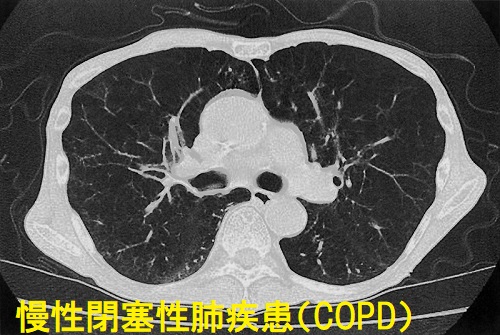

甲状腺機能亢進症/バセドウ病の甲状腺ホルモン過剰状態では、甲状腺ホルモンの交感神経刺激作用で気管支は拡張し、COPD(慢性気管支炎、肺気腫)がマスクされます。

甲状腺機能亢進症/バセドウ病を治療し、甲状腺ホルモンが正常化すると、拡張していた気管支が元に戻るためCOPD(慢性気管支炎、肺気腫)の出現/再発/増悪が起こります。

逆の報告もあり。甲状腺機能亢進症/バセドウ病では、甲状腺ホルモンの異化亢進(蛋白分解)により呼吸筋力が低下し、呼吸機能が悪化。治療により甲状腺ホルモンが正常化すると回復します。(Am Rev Respir Dis 1992;146:1025-9.)(Adv Respir Med 2017;85:28-34.)

COPDの治療は、長時間作用型ベータ2刺激薬・長時間作用型抗コリン薬(第一選択)・徐放性テオフィリン薬等を重症度に応じて併用。甲状腺機能亢進症/バセドウ病が隠れていたり、治療中でも甲状腺ホルモンが正常化していないと、交感神経が刺激され

を誘発する危険があります。急性増悪繰り返す場合、吸入ステロイド剤も併用します。これらは進行を抑制できませんが呼吸困難・運動耐容能は改善します。